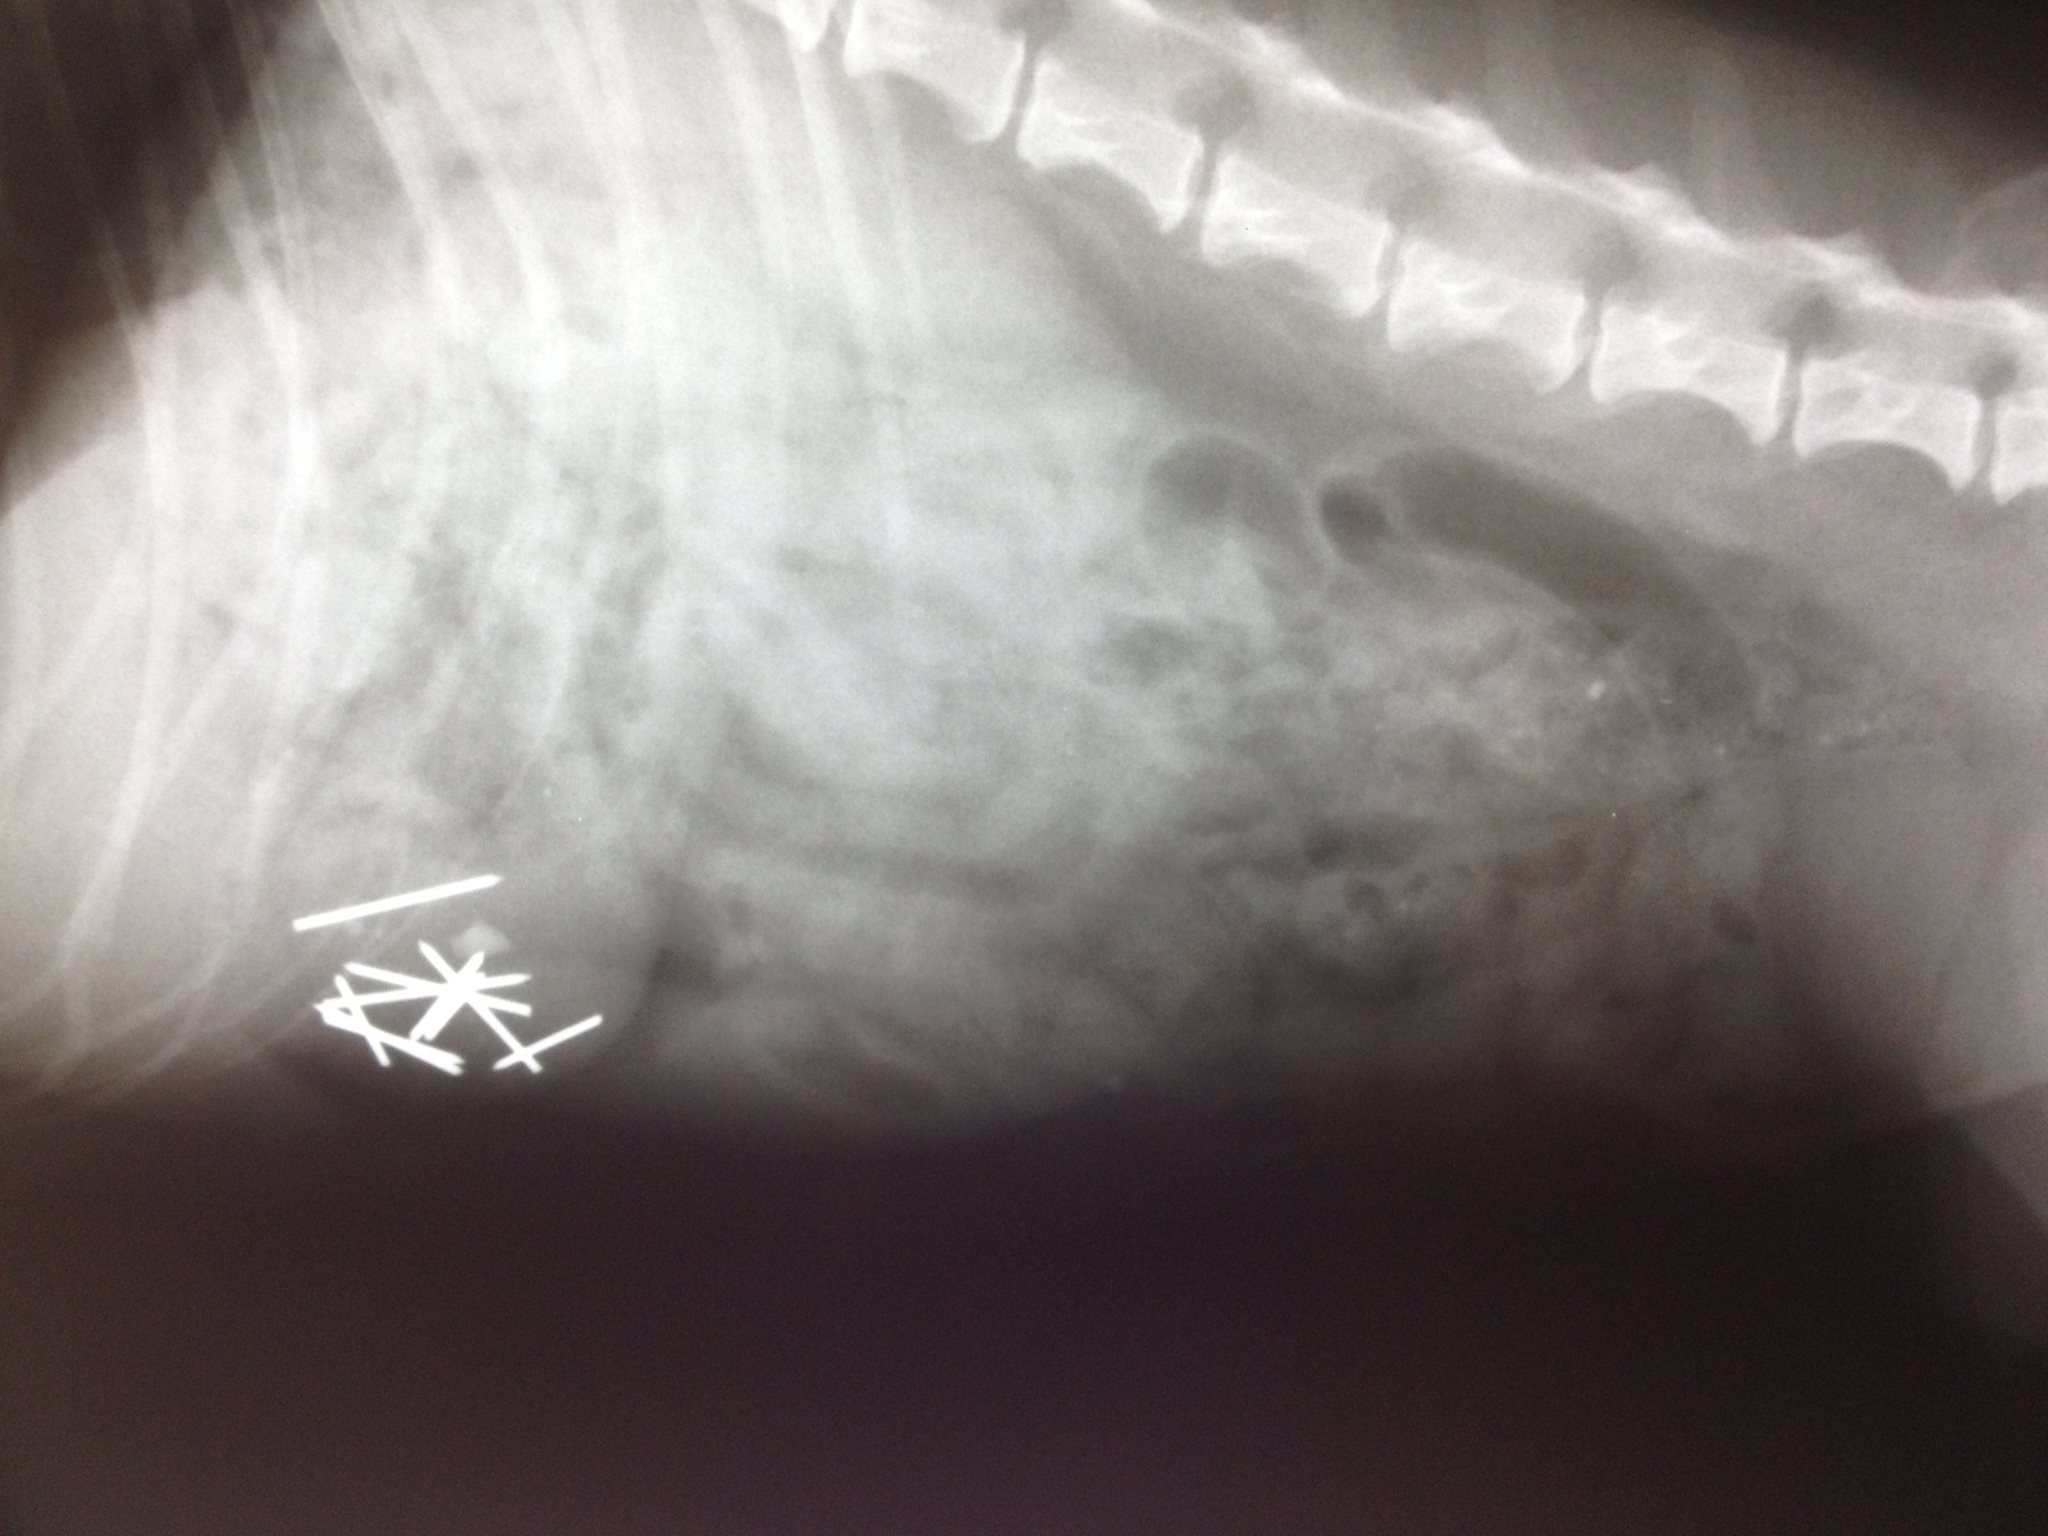

La redazione di Vnews24 ha raggiunto il padrone di una delle “vittime”, che, ancora shoccato da quanto accaduto alla sua cagnolina, ci ha descritto la situazione così: “Non sappiamo cosa stia succedendo. La mia cagnolina è quasi morta per colpa di questa persona che ha deciso di uccidere quanti più animali possibili del paese“. La nostra fonte ci ha raccontato che, durante la passeggiata mattutina, il suo cane ha mangiato un boccone di cibo trovato per strada. Per fortuna, la nostra fonte ha notato un altro di questi “bocconi ripieni” e lo ha raccolto per esaminarlo. Tornato a casa, l’amara sorpresa: il cibo conteneva decine di chiodi di circa 2 cm di lunghezza ciascuno. “Ho portato subito il cane a fare una lastra, e per fortuna sono arrivato in tempo. Il mio cane aveva ingerito un pezzo di cibo contente dieci chiodi. Se fossi arrivato troppo tardi dal veterinario, sarebbe morto tra atroci sofferenze“.